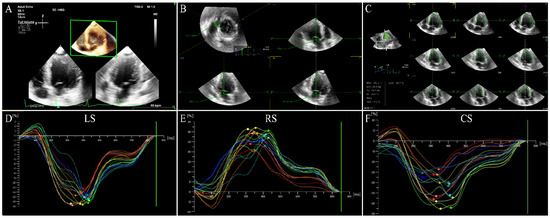

6.1. Left Ventricular Global Systolic Function

6.2. Left Ventricular Regional Systolic Function